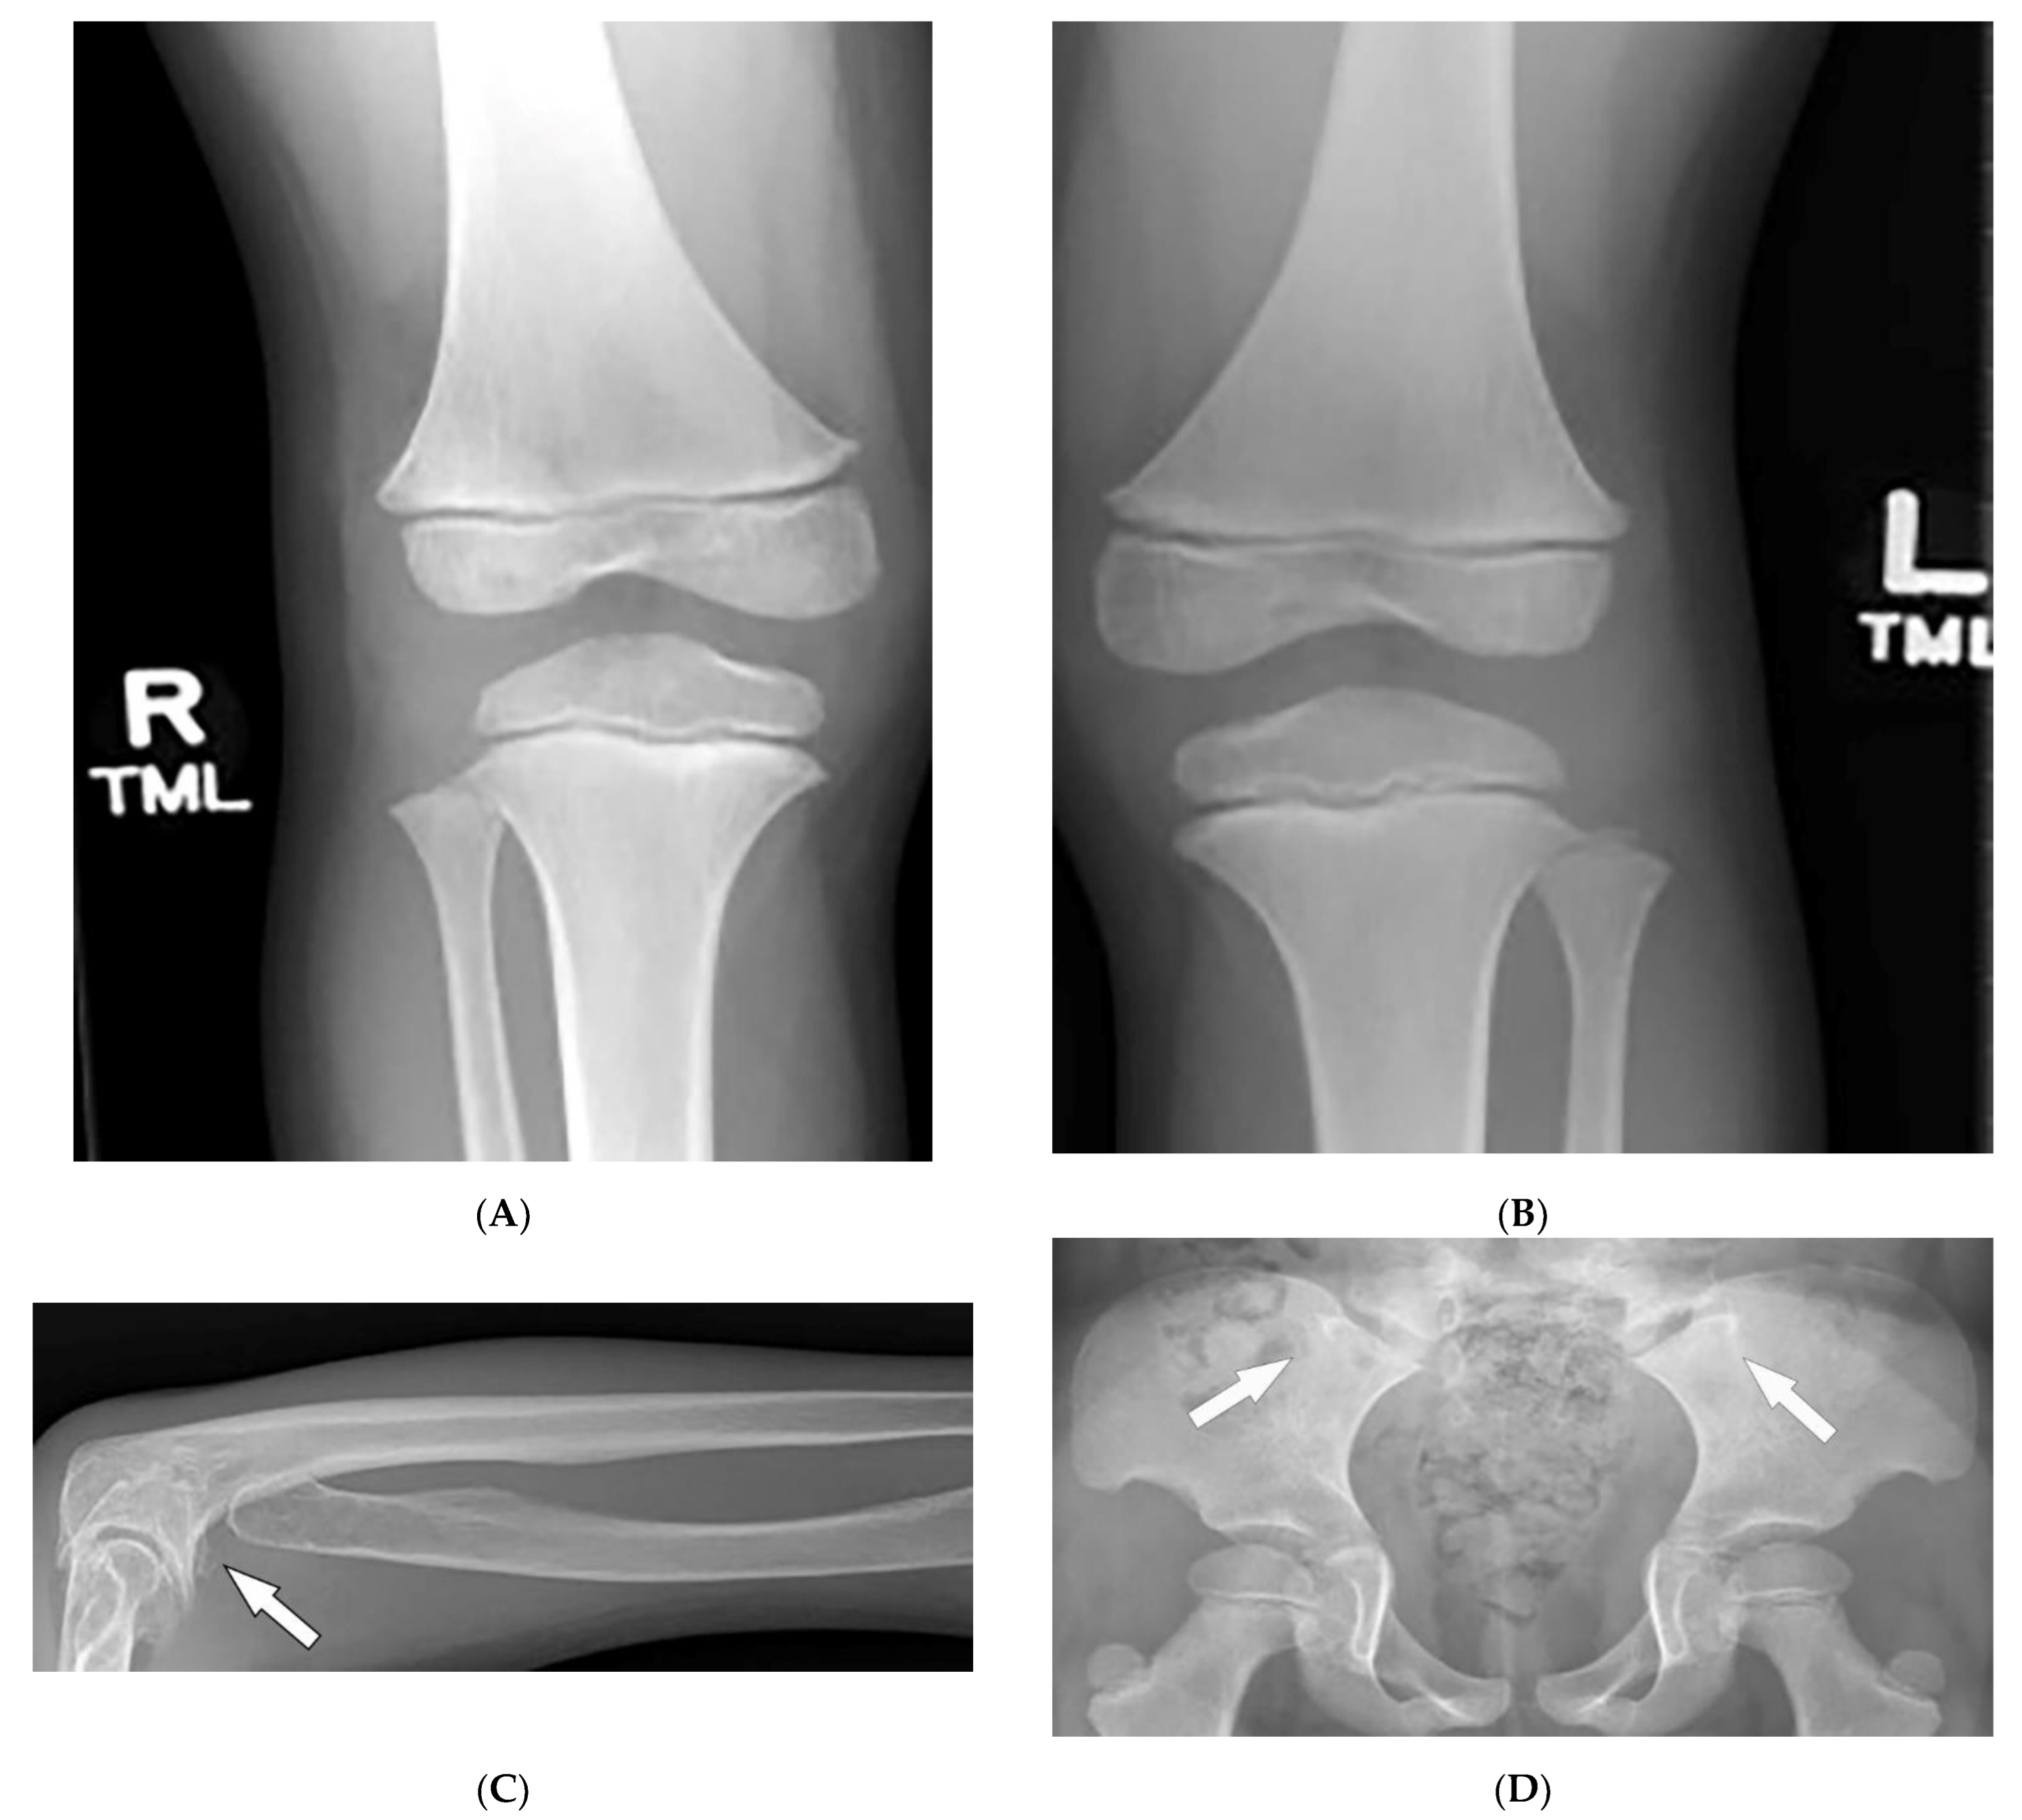

| Fong (Nail–patella) syndrome | Hypoplastic nails, triangular lunulae Hypoplastic patellae Focal segmental glomerulosclerosisLester iris | Bilateral absence of patellae Posterior iliac horns (Fong’s prongs) Subluxation of radial heads |